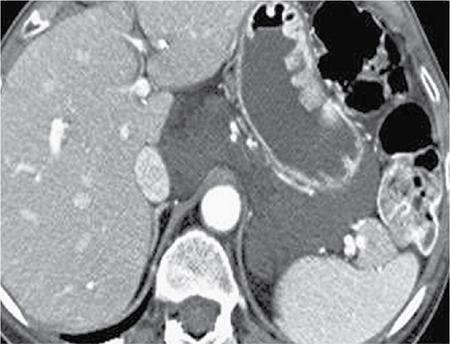

Image

Fig. 10.17.1.3 Contrast-enhanced axial CT sections in a case of acute pancreatitis (asterisk in A); the pancreas appears diffusely bulky with peripancreatic fat stranding. Thickening of the anterior renal fascia (blue arrows in B and C) with fluid collection in the anterior pararenal space (blue arrow in D).